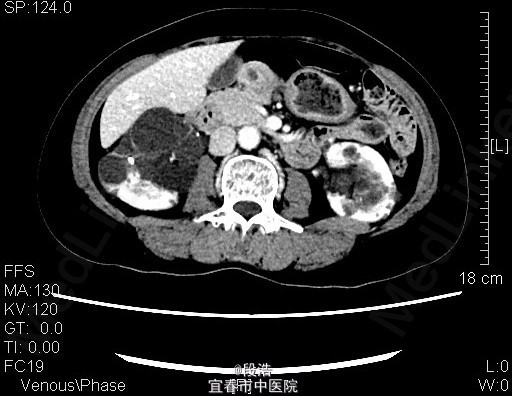

1、中年女性,体检发现双侧肾囊肿2年 2、患者于2年余前至当地医院体检发现双侧肾囊肿,当时诉腰部稍酸胀,尿量稍增多,无尿频、尿急、尿痛,无排尿困难,无血尿、脓尿等。起病以来,患者一般情况尚可,体重无下降

3、查体:未见明显异常 4、辅助检查:2013-4-11我院中腹部CT结果考虑多囊肝(未给出图像),双侧多囊肾,双肾囊壁部分钙化;双肾多发结石。2015年5月复查结果同前。

5、诊断:多囊肝,双侧多囊肾,双肾多发结石 6、入院后完善相关检查,生化,心电图,胸片未见异常,复查ct提示多囊肝,双侧多囊肾,双肾囊壁部分钙化;双肾多发结石,排除手术禁忌症后,行腹腔镜下左肾囊肿去顶术,术后予“注射用头孢美唑钠(先锋美他醇)”抗感染、抑酸、静脉营养补液等处理,术后恢复良好,顺利出院。术后半年复查再决定另一侧的处理方式。